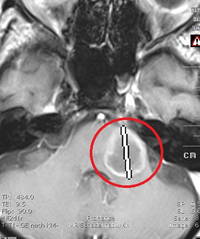

In einem aktuellen Fall zeigen wir Ihnen im linken Bild die Aufnahme von einer Hirnstamm-Metastase, die 2016 bei einer Patientin diagnostiziert wurde. Primärtumor war ein Adenokarzinom der Lunge. Die Patientin wurde im Mai 2016 mit Cyberknife in typischer Einzeitsitzung radiochirurgisch behandelt. Auf Grund der kritischen Lage am Hirnstamm und Größe der Metastase wurde die Dosis auf 17 Gy (70 Prozent Isodose) reduziert. Knapp ein Jahr nach der Behandlung ist die Metastase bildgebend ausgeschaltet, es zeigt sich nur noch eine Narbe (Bild rechts).